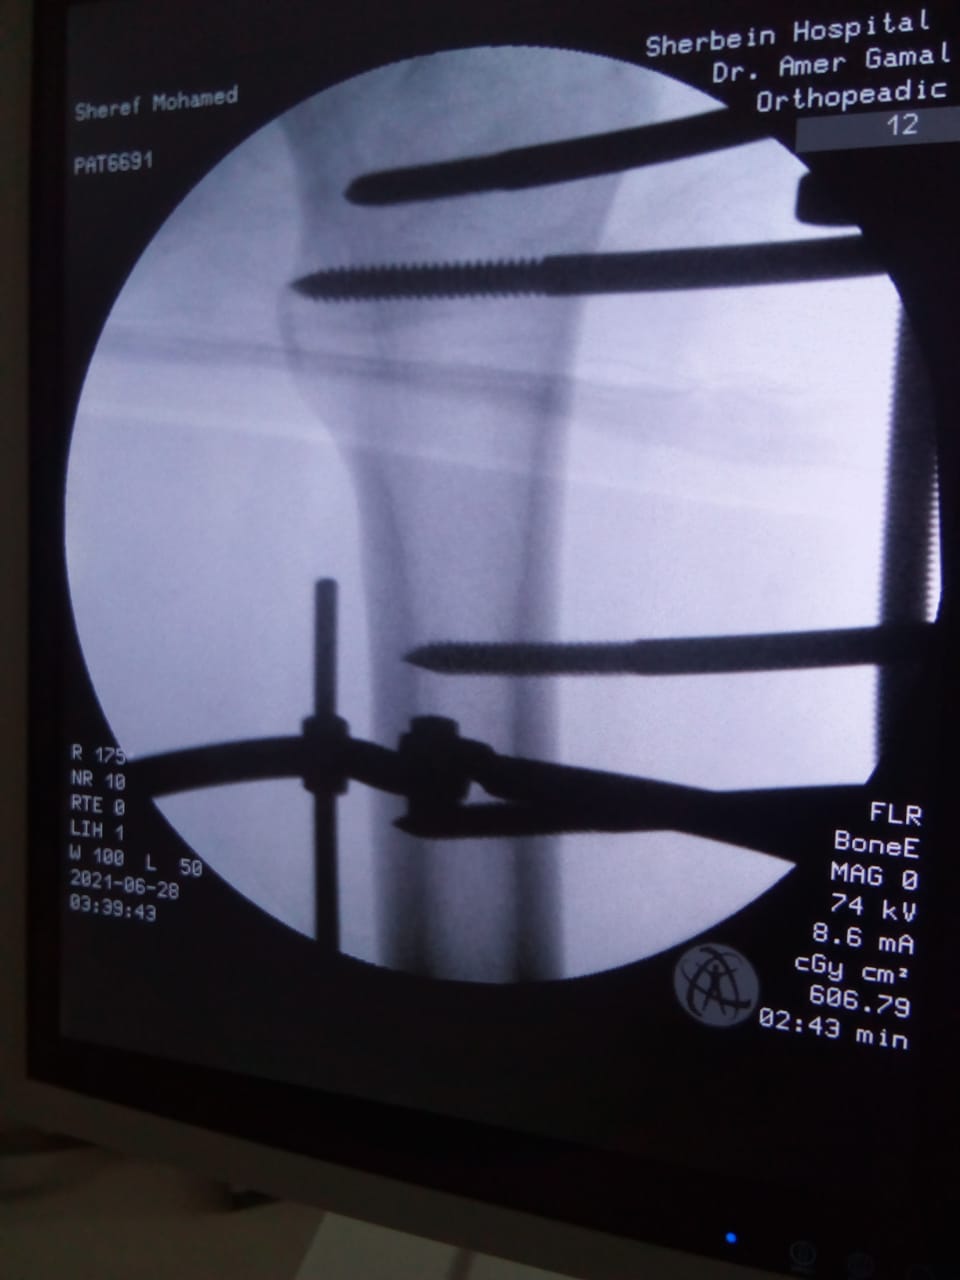

أعلن الدكتور سعد مكي، وكيل وزارة الصحة بالدقهلية، مساء اليوم، نجاح فريق طبي في إجراء تدخل جراحي دقيق لشاب يعاني من كسر مضاعف من الدرجة الثالثة إثر طلق ناري أدى إلى تهتك بالأنسجة وكسور متفتتة بالفخذ.

وتمكن الفريق الطبي من إجراء الجراحة عن طريق جهاز الليزاروف في واحدة من عمليات العظام الكبرى بمستشفى شربين المركزي، وهي تعد من العمليات المتقدمة ذات المهارة الخاصة.